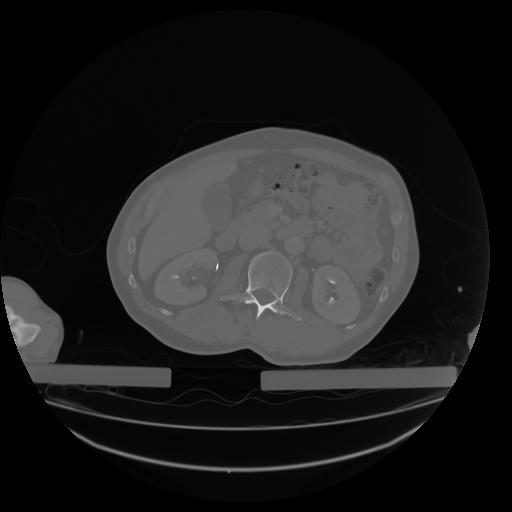

27 CUERPO,CE,Axial,3.0,CUERPO,,